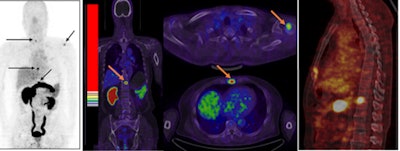

The paper outlines the first-in-human application of a peptide BBN-RGD agent labeled with gallium-68 (Ga-68) that targets gastrin-releasing peptide receptor (GRPR) and integrin αvβ3. Results suggest that Ga-68 BBN-RGD is both safe and effective (JNM, February 2017, Vol. 58:2, pp. 228-234).

The study included four patients who were newly diagnosed with prostate cancer, nine patients who had received therapy, and five healthy volunteers. Ga-68 BBN-RGD PET/CT detected 20 bone lesions in seven patients either with primary prostate cancer or after radical prostatectomy.